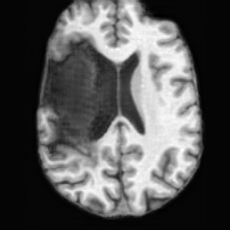

PathologicalHealthyDifferencew/o ACGw/ ACG(a)Refer to captionRefer to captionRefer to captionRefer to captionRefer to captionHealthyPathologicalDifferencew/o ACGw/ ACG(b)Refer to captionRefer to captionRefer to captionRefer to captionRefer to caption

Figure 6: Ablation study of Anatomy Consistency Guidance (ACG): (a) pathology-to-healthy; (b) healthy-to-pathology. Without ACG, edits cause anatomical inconsistencies outside lesions (arrows), whereas ACG keeps modifications lesion-focused.

Anomaly Consistency Guidance. Fig. 6 demonstrates the effectiveness of the proposed Anatomy Consistency Guidance (ACG) on bidirectional editing. Without ACG, the generated brains exhibit noticeable and unrealistic anatomical deformations in non-lesion regions (arrow-indicated), leading to structural inconsistencies between the edited and original brains, as shown in the corresponding difference maps. After incorporating ACG, the model effectively constrains editable modifications within pathological regions, while preserving the remaining anatomy. Tab. 4 further reports their quantitative performances: removing ACG leads to a substantial degradation in all L1, PSNR, and SSIM scores, reaffirming the critical role of ACG in achieving more accurate and structurally consistent reconstructions.